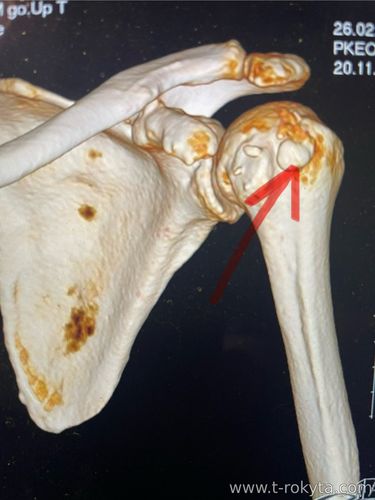

Кальцифікуючий тендініт плеча ( по народному звучить як "солі відкладуються ") є досить частим захворюванням плечового суглобу. При цьому вражуються сухожилки ротаторної манжети плеча (РМП), що веде до різкого обмеження рухів та вираженого больового синдрому. В діагностуванні цієї проблеми відіграють рентгенологічне дослідження, мрт та кт плечового суглобу. Артроскопія плечового суглобу дозволяє повністю вилікувати цю проблему